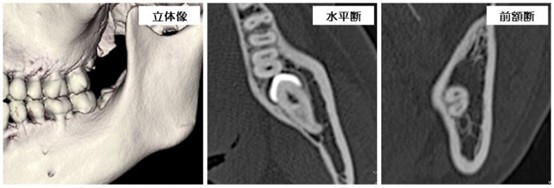

初診時に口腔内の診査やレントゲンで顎骨や歯の状態を検査します。必要に応じてCT検査(X線を用いた断層画像)を行い、顎骨の状態や歯の形および方向や位置、周囲の神経や血管との位置関係等を三次元的に評価した上で抜歯計画を立てています。

CT画像